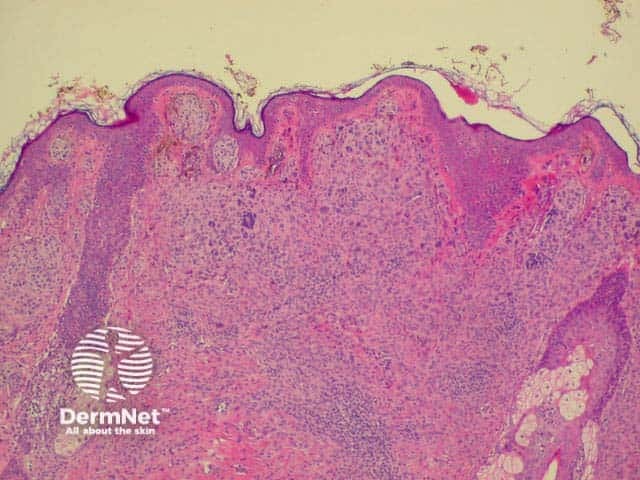

Histology is shown below.

Histology of intradermal naevus Superficial epithelioid naevus cells Deeper small dark naevus cells